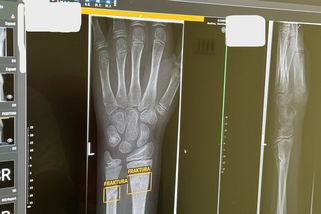

Úvodní fotka